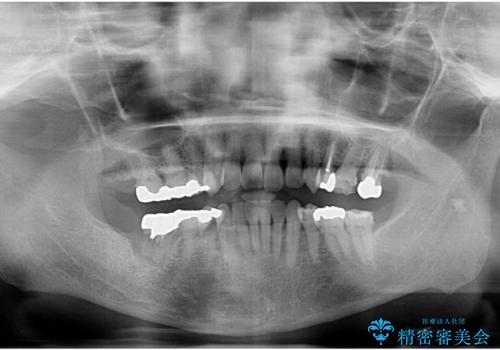

X線、歯周組織検査の結果、全体的に奥歯には重度〜中等度の歯周病の問題が見られました。

残すことのできない歯、予後の悪い歯を抜去し、ブリッジイ・ンプラントによる機能回復をおこなっていくと同時に、残すことのできる歯には歯周病治療をしっかりと行い、

将来に渡りしっかりと自分の歯で噛めるような口腔内環境を構築していきます。